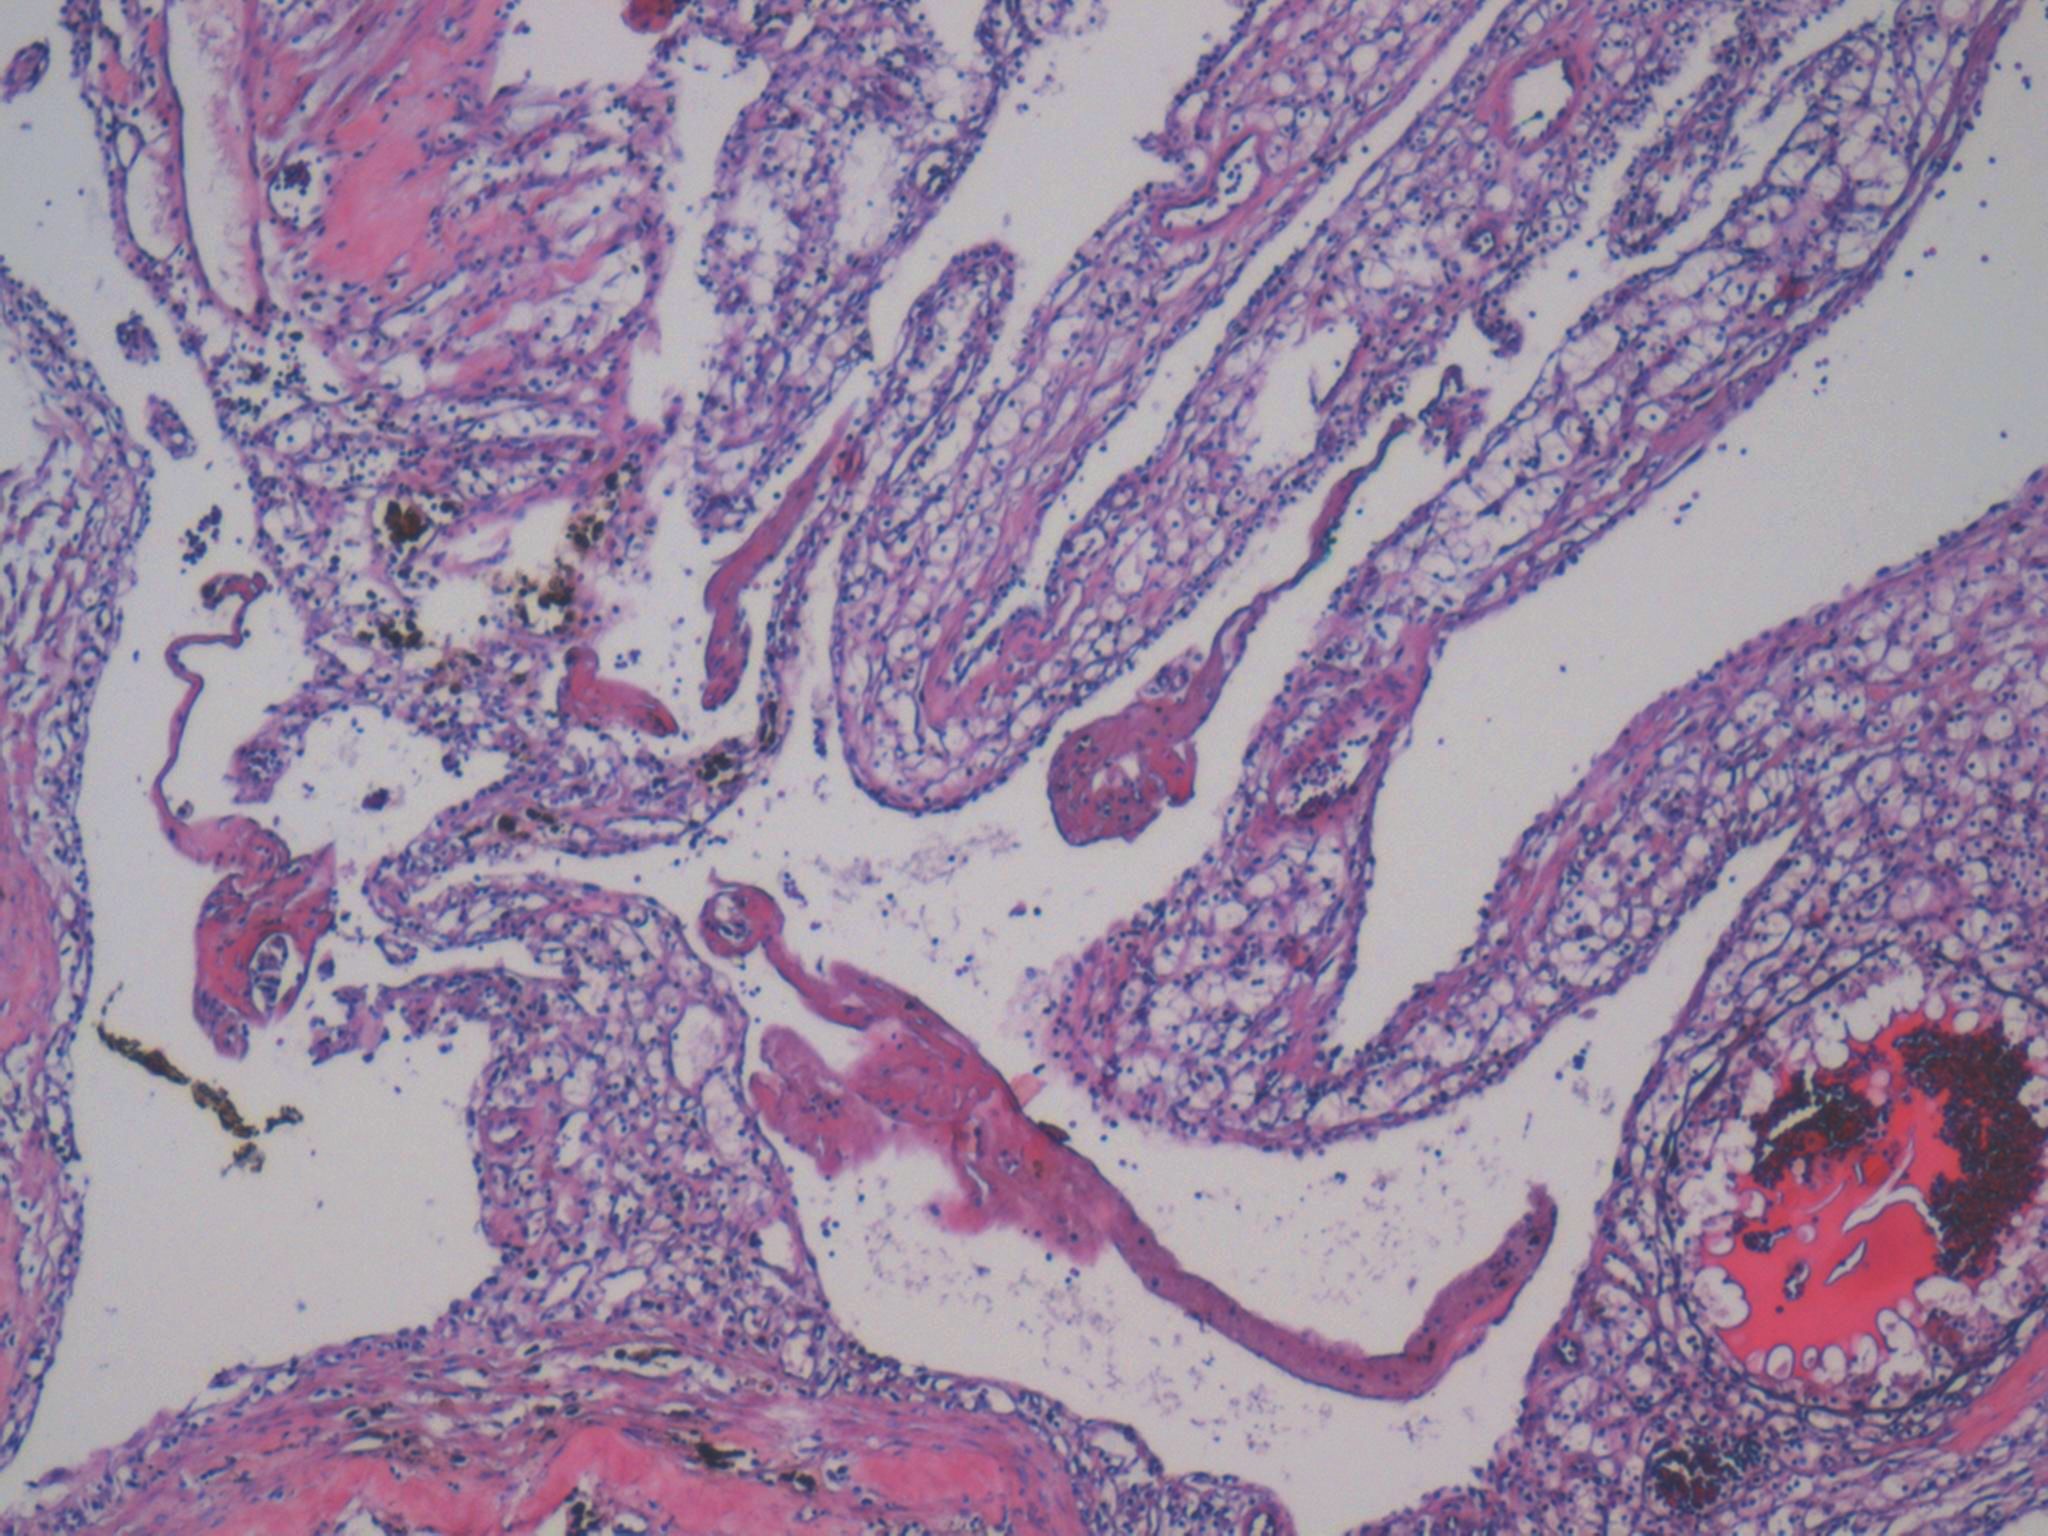

Renal tumor grading

Case ID: 1104